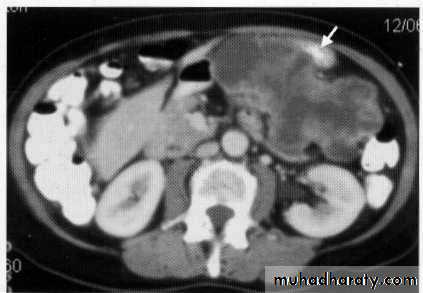

Peritoneal deposit